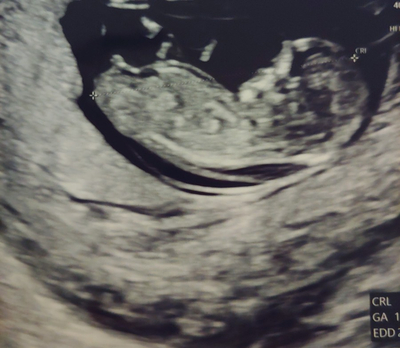

- 1차 정밀초음파&통합 선별검사 임신 12주차는 중요한 시기이고, 아이가 상당히 커서 배의 초음파가 가능해져 1차 정밀 초음파 검사와 통합 선별검사를 시행합니다.

- 정밀초음파는 1차(10~13주), 2차(20~21주)에 이루어지는데, 1차 정밀초음파검사 : 태아의 목투명대(NT) 두께 측정을 통해 태아의 염색체, 심장에 이상이 없는지 확인합니다.보통 2.5mm 미만이 정상입니다 (목투명대란, 아기를 둘러싼 양막에서 목에 걸친 뚫린 부분입니다 )